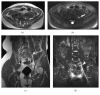

Magnetic resonance neurography is a high-resolution imaging technique that allows evaluating different neurological pathologies in correlation to clinical and the electrophysiological data. The aim of this article is to present a review on the anatomy of the lumbosacral plexus nerves, along with imaging protocols, interpretation pitfalls, and most common pathologies that should be recognized by the radiologist: traumatic, iatrogenic, entrapment, tumoral, infectious, and inflammatory conditions. An extensive series of clinical and imaging cases is presented to illustrate key-points throughout the article.